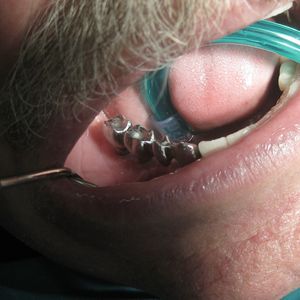

Prosthetic rehabilitation: once osseointegration is complete, an abutment and permanent crown, bridge, or denture is placed on the implant. Prosthetic rehabilitation on implants is our core specialty and is key to the long-term success of the treatment.